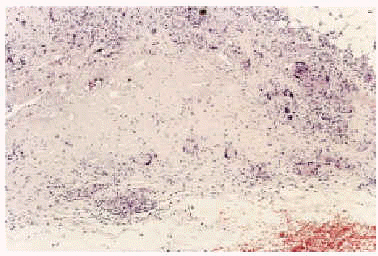

Realizamos biopsia de uno de los nódulos, que mostró la existencia en dermis profunda y septos hipodérmicos de amplias zonas de necrobiosis del colágeno (fig. 2), que formaban granulomas en empalizada rodeados por abundantes células gigantes multinucleadas (fig. 3), lo que llevó al diagnóstico de paniculitis septal por necrobiosis lipoídica.

Fig. 3.--Detalle de un foco de necrobiosis en el que se aprecia la degeneración del colágeno rodeada por una empalizada de histiocitos y células gigantes multinucleadas.